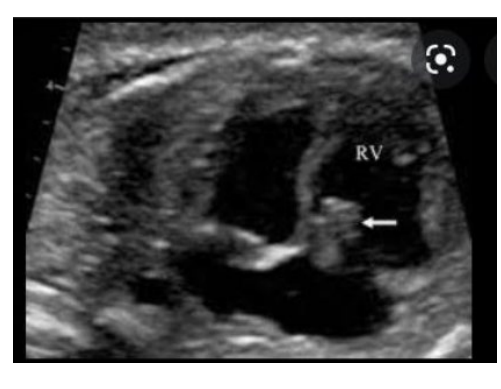

Myxoma, arises from the what?

Most frequently in what chamber (?%) and what other chamber (?%)

Attached to the what by a what?

Arises from the endocardium •

Most frequently in left atrium (75%) and right atrium (25%) •

Attached to the fossa ovalis by a pedicle

Myxoma, may cause what insufficiency?

Postnatally they are associated with what?

May cause what and require surgical resection?

May cause AV valve insufficiency

Postnatally they are associated with emboli

May cause CHF and require surgical resection